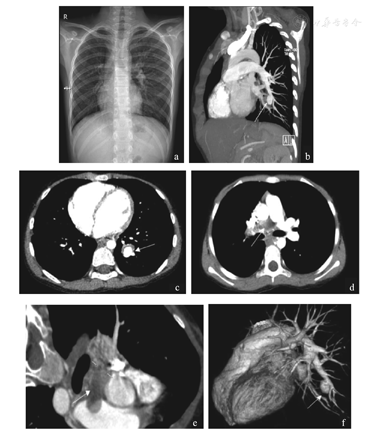

入院后检查:血常规:WBC 11.24×109/L,N 60.6%,L 31.4%,Hb 118 g/L,PLT 213×109/L;CRP 91.3 mg/L;ESR 53 mm/h;PCT 0.39 ng/ml;凝血功能:APTT 41 s(24~36 s),PT 15 s(9~14 s),INR 1.3(0.8~1.2),FIB 4.69 g/L(2~4 g/L),D-二聚体584 μg/L(0~550 μg/L);动脉血气分析:pH 7.44,PCO2 29.1 mmHg,PO2 71 mmHg,HCO3 20.3 mmol/L,SO2 95.2%,FiO2 41%;RSV和MP-IgG、IgM均阳性;结核抗体、T-SPOT、真菌抗原、真菌G实验、HIV抗体、梅毒抗体、自身免疫抗体、肿瘤标记物七项、痰培养、血培养、骨髓培养均阴性;骨髓涂片:感染性骨髓象。心脏超声正常;纤维支气管镜检查示左下叶后基底段有一约0.5 cm×0.5 cm大小占位,堵塞部分气道。胸部正位片:双肺纹理增多,左肺纹理稍模糊,可见点状渗出模糊影,见图1a。胸部增强CT+肺动脉造影(三维重建):(1)右肺动脉主干肺栓塞;(2)支气管动脉扩张;(3)左下肺动脉分支动脉瘤伴附壁血栓形成;(4)两肺多发斑片影,两肺条索灶;(5)两侧胸膜局限增厚,见图1b,图1c,图1d,图1e,图1f。诊断:(1)重症肺炎;(2)左下肺动脉分支动脉瘤并附壁血栓形成;(3)右肺动脉主干肺栓塞;(4)支气管动脉扩张。

a.胸部正位片;b.多平面重建图(箭头示左下肺动脉分支动脉瘤并附壁血栓);c.左下肺动脉分支动脉瘤并附壁血栓形成;d.右肺动脉主干肺栓塞;e.多平面重建图(箭头示右肺动脉主干肺栓塞);f.三维重建。